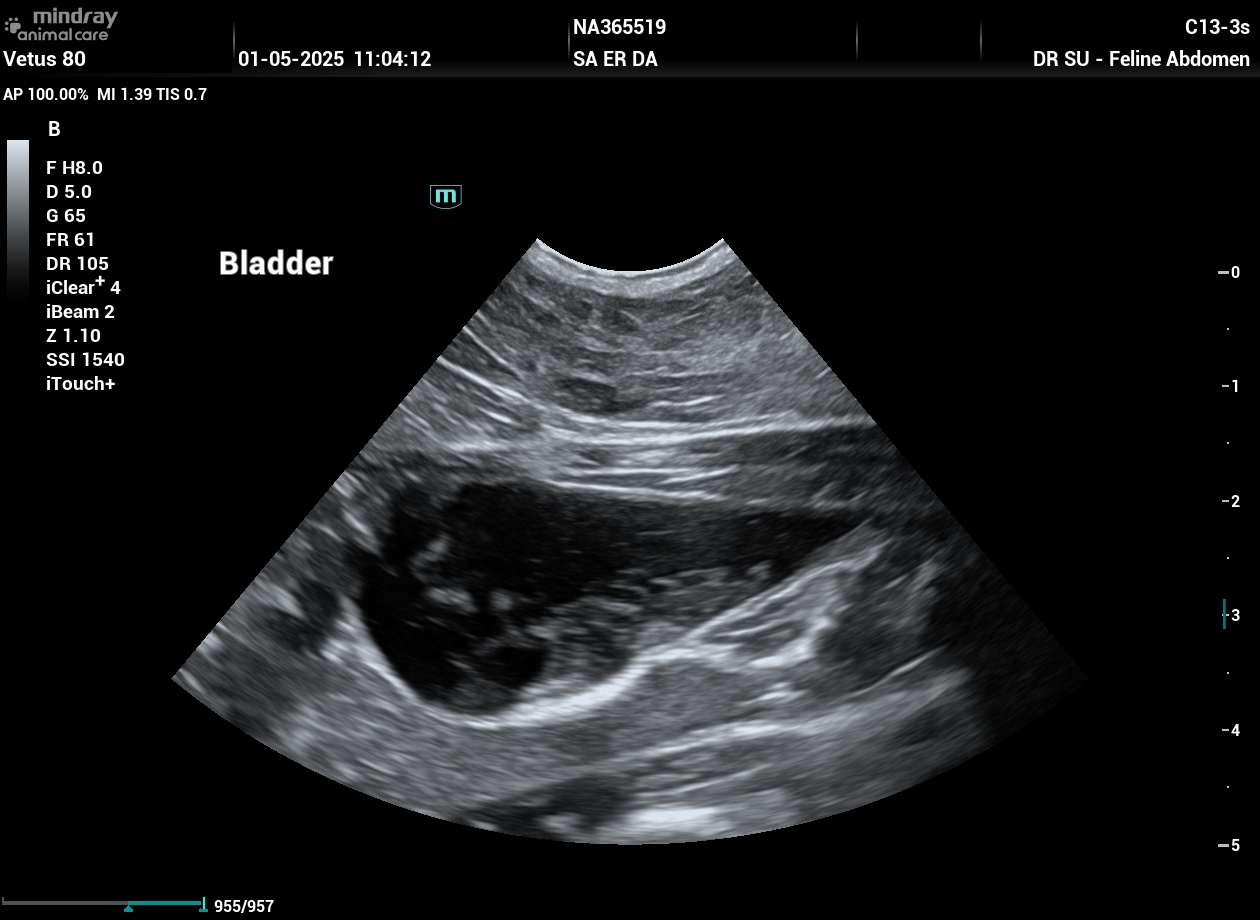

202505011104270025ABD.JPG